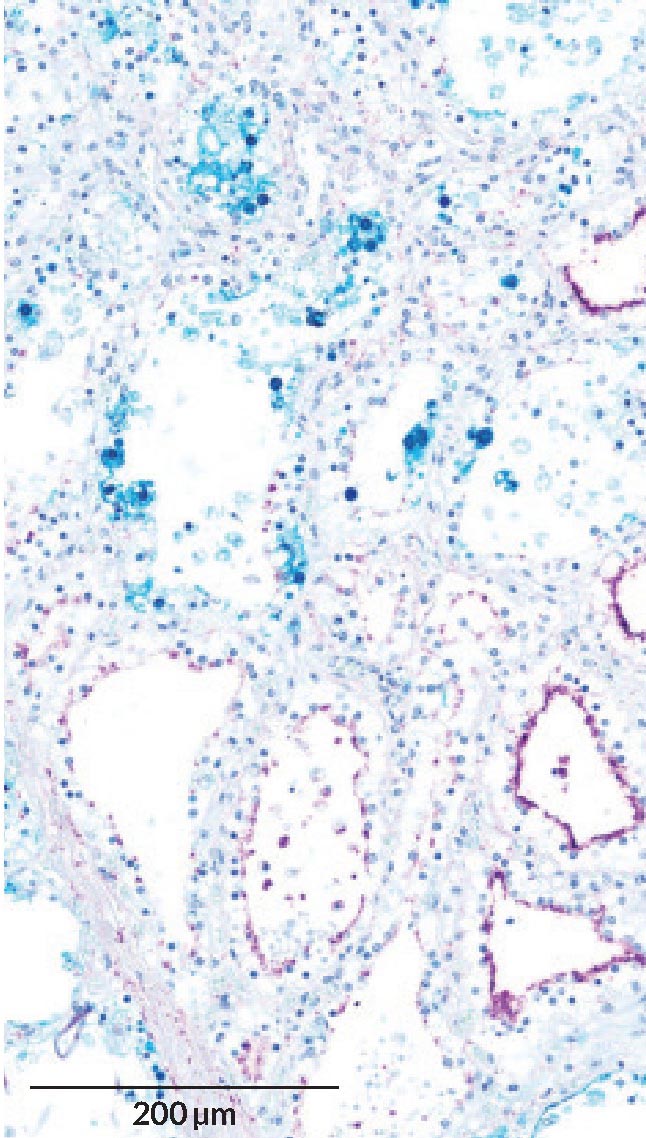

Клетки молочной железы коровы имеют на своей поверхности специфические сахара (на микроскопическом изображении они показаны фиолетовым цветом), которыми вирус H5N1 (синий) пользуется для проникновения и развития инфекции.

Чтобы проникнуть в клетки молочной железы коровы, вирус использует молекулы сахара на поверхности клеток, как сообщают исследователи в июльском выпуске Emerging Infectious Diseases (2024). Оказавшись внутри, вирус может попадать в молоко. Подобные инфекции, вероятно, объясняют распространение вируса среди скота: заражённое доильное оборудование может переносить его от вымени одной коровы к другой.